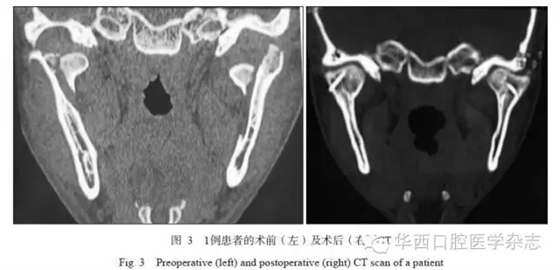

在24側(cè)SFMC中,有2例患者出現(xiàn)暫時性面神經(jīng)損傷,主要表現(xiàn)為額皺變淺,半年后均恢復(fù)正常;其余無術(shù)中和術(shù)后并發(fā)癥。術(shù)后X線全景片或CT檢查顯示:骨折段對位良好,無旋轉(zhuǎn)移位情況發(fā)生,髁突形態(tài)正常(圖3);無鈦板及螺釘松脫、扭曲或折斷。術(shù)后咬合關(guān)系恢復(fù)良好,開口度及開口型恢復(fù)正常。